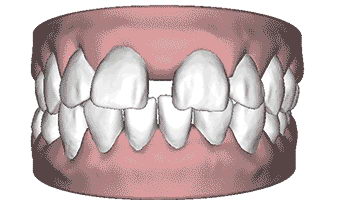

▲需要拔除的四颗牙齿

整个手术过程需要口腔科医生和颌面外科医生的紧密协诊和配合,制定出较适合患者情况的手术方案。